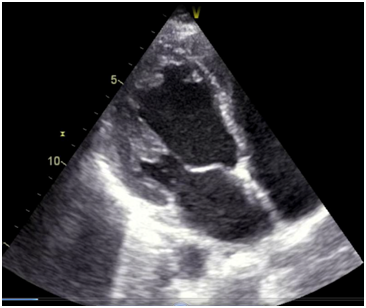

Her echocardiographic findings before supplementing calcium. Her LVIDD/S-5.2/4.5cms and IVSD/S-1.2/2 pwd/s-1.0/1.2 her ejection fraction was -26%. Her aorta/la dimension was 4/2.8.On treatment she improved .But on repeat echo she was found to have an left ventricular apical clot but her ejection fraction improved to 48 % (Figure 3).

Gardner et al.,22 have described the ECG changes in both hypocalcaemia and Hypercalcemia. Hypocalcaemia causes on lengthening of the QT segment or QT prolongation they also report that those with a corrected QTc of more than 500 msecs have an increased chance of arrhythmias (Figure 4) (Figure 5). Various authors have also described hypocalcaemic cardiomyopathy in different cases that reversed with treatment.23–26

Figure 4 The gradually improving left ventricular function of the patient on correcting the QT interval , and her left ventricular apical clot.